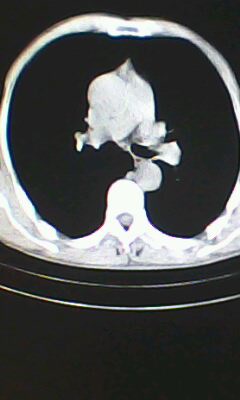

标题: CT26182:男 胸憋 无其它异常症状

胸廓呈桶状,双膈低平,肺实质及纵隔未见明显异常密度灶考虑肺气肿.

肺气肿

临床诊断:copd

慢阻肺是临床诊断,未见明显异常。